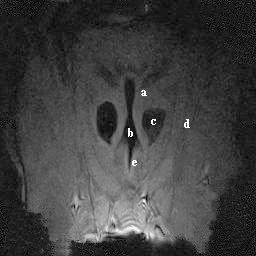

A study was performed to establish the appearance of normal equine laryngeal cartilages using magnetic resonance imaging. Specimens were acquired from clinically normal horses that were euthanized for reasons other than respiratory disease. Three in situ and 5 ex vivo larynges were imaged using a 0.3 Tesla system. Images were obtained in the transverse plane using T1-weighted 3D spin echo, T2-weighted 3D spin echo, T2-weighted gradient echo, short tau inversion recovery (STIR), and proton density spin echo sequences. Five ex vivo larynges were also imaged in the transverse plane using a 1.5 Tesla system, sequences included T1-weighted 3D spin echo, T2-weighted 3D turbo-spin echo, turbo inversion recovery (TIRM), and proton density spin echo sequences. A frozen gross laryngeal specimen was sliced in 5-mm transverse sections for comparison to the MR images. Excellent correlation was found between MR images and the gross transverse sections. Successful imaging was accomplished using both imaging systems; however, the 1.5 Tesla system yielded superior image resolution. The 0.3 Tesla imaging system would accommodate the intact equine head, which was not possible using the 1.5 Tesla MRI system. The internal morphology of the laryngeal cartilages was clearly identified in all imaging sequences obtained. Cartilages were found to differ in signal intensity based on the tissue composition and imaging sequences performed. MRI was determined to be a useful imaging modality for evaluating the cartilage morphology of the equine larynx. Further investigation is required to document pathologic morphology.